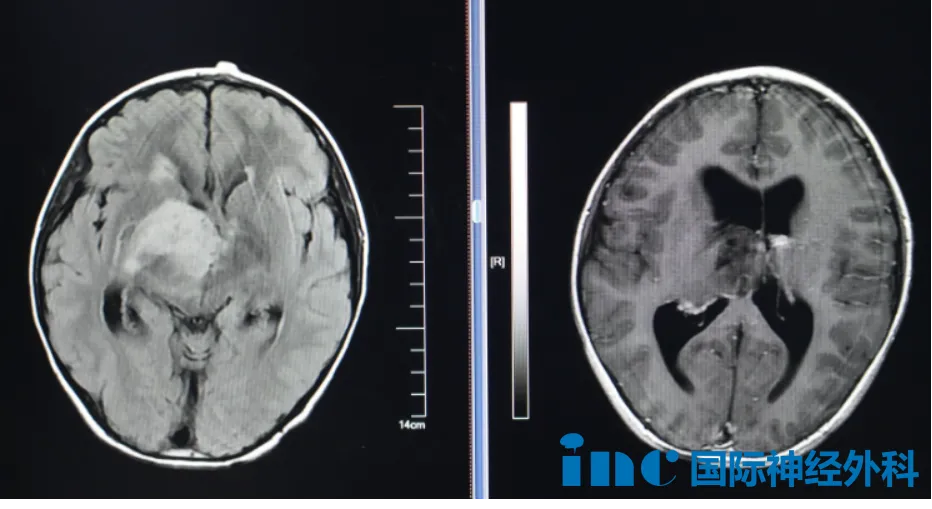

病例详情一:8岁男性疑似弥漫性胶质瘤

8岁男性患儿小航,今年10月因外伤于当地医院行头部CT检查,意外发现右侧丘脑、基底节区占位性病变,合并梗阻性脑积水。病灶尺寸约4.0cm×4.7cm×4.8cm,考虑弥漫中线胶质瘤可能性大。患儿临床表现包括偶发记忆力下降、注意力不集中、饮水呛咳。

面对如此大体积肿瘤及危急情况,下一步诊疗方向成为关键。巴特朗菲教授评估后给出明确建议:患儿存在明确手术指征,应尽快接受手术,不宜延迟。关于胶质瘤性质,巴教授表示可能为低级别胶质瘤,但需等待最终手术病理结果确认。这一评估为一直担忧的家长带来了希望。